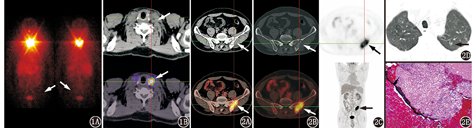

患者男,50岁。无明显诱因出现左侧腰臀部及左下肢内侧疼痛,多出现于行走或挤压时,呈钝痛,休息后可减轻,无发热,无下肢静脉曲张、肿胀、水肿,未予治疗,现左下肢疼痛加重。既往无外伤、肝炎、结核病史。实验室检查:癌胚抗原(carcinoembryonic antigen, CEA)7(0~5;括号内为正常参考值范围,下同) μg/L,余肿瘤标志物均为阴性;WBC计数8.4(3.5~9.5)×109/L,RBC计数4.5(4.3~5.8)×1012/L,Hb 133(130~175) g/L,中性粒细胞百分比66%(40%~75%);抑制治疗状态下甲状腺球蛋白(thyroglobulin, Tg)2.2(3.5~77.0) μg/L,游离三碘甲状腺原氨酸(free triiodothyronine, FT3)5.00(3.28~6.47) pmol/L,游离甲状腺素(free thyroxine, FT4)17.2(7.9~18.4) pmol/L,促甲状腺激素(thyroid stimulating hormone, TSH)1.16(0.34~5.60) mU/L。该患者10个月前因甲状腺乳头状癌(papillary thyroid cancer, PTC)于本院行"右侧甲状腺癌扩大根治术+左侧甲状腺近全切除术+双侧颈部淋巴结清扫术"。7个月前于本院行131I清除残留甲状腺组织(简称清甲)治疗(剂量4 440 MBq),清甲治疗前血清TSH 84.53 mU/L,Tg 15.0 μg/L,甲状腺球蛋白抗体(thyroglobulin antibody, TgAb)<10(0~115)×103 U/L。清甲治疗后1周行131I SPECT/CT显像,结果(图1)示甲状腺区摄碘灶,颈部以外其他部位未见异常摄碘组织。3个月前停服左甲状腺素钠片,停服1个月后查血清Tg为4.2 μg/L,该患者因个人原因未行停药后小剂量碘扫描。现甲状腺彩超提示甲状腺双叶切除术后,双侧颈部未见明显异常肿大淋巴结。为明确全身情况及下肢疼痛原因,行18F-脱氧葡萄糖(fluorodeoxyglucose, FDG)PET/CT[德国Siemens Biograph Truepoint64 (52环)]显像,结果(图2)示左侧髂骨不规则斑片状骨质破坏并局部片状软组织影形成,病变区FDG摄取异常增高,最大标准摄取值(maximum standardized uptake value, SUVmax)约13.0;病变区大部分呈溶骨性表现,局部见点片状碎骨块影及线样硬化边;双肺上叶另见多个高密度小结节影,放射性分布未见异常;全身其他部位未见FDG摄取异常增高灶。后行CT引导下左髂骨病变穿刺活组织检查,病理检查(图2E)示广泛朗格汉斯细胞浸润。免疫组织化学检查:甲状腺转录因子-1(thyroid transcription factor-1, TTF-1;-),细胞角蛋白(cytokeratin, CK;个别+),CD68(+),平滑肌肌动蛋白(-),P63(-),细胞增殖核抗原Ki-67(+;10%~20%),S-100蛋白(+),富含AT序列的特异性结合蛋白2(special AT-rich sequence-binding protein 2, SATB-2蛋白;-),CD207(+),CD1a(+),提示朗格汉斯细胞组织细胞增生症(Langerhans cell histiocytosis, LCH)。

骨骼系统是LCH最常侵及的部位,LCH发生于骨骼者多见于颅骨、脊柱、肋骨及四肢长骨等[2],而发生于髂骨者罕见。LCH的病因目前尚无定论,尽管不少研究考虑其发病与病毒、免疫学等有关,但至今尚无明确证据。实验室检查伴嗜酸性粒细胞升高,血红细胞沉降率加快;免疫组织化学检查CD1a、S-100蛋白和CD207阳性是重要的诊断证据[3],部分患者可伴有CD68阳性。CT主要表现为骨骼呈单发或多发溶骨性骨质破坏,多起于病灶中心,部分可见线样硬化边,部分见死骨、骨膜反应及软组织肿胀[4]。此外,增殖朗格汉斯巨细胞及淋巴细胞等均具有高葡萄糖代谢活性,所以骨LCH在18F-FDG PET/CT上多表现为FDG摄取明显增高,本例表现与之相符。本例左侧髂骨病变单从CT图像特征来看,病变区大部呈溶骨性表现,局部见点片状碎骨块影及线样硬化边,周围软组织变化不显著,亦不明确支持原发或转移性恶性肿瘤所致,多考虑良性或低度恶性骨病变,这也与LCH骨骼侵犯的CT表现相符。

本例18F-FDG PET/CT显像示双肺上叶多个高密度小结节未见明显FDG摄取增高,亦不高度怀疑恶性病变,但不排除甲状腺癌肺转移。肺是PTC最常见的远处转移部位,肺转移是甲状腺癌患者最主要的致死原因[11]。与患者清甲治疗后131I SPECT/CT融合图像比较,双肺上叶多个高密度小结节为新发病变,但由于患者Tg、TgAb水平始终未见增高,因此不支持甲状腺癌肺转移。肺部LCH发病率仅次于骨,X线及CT早期表现为1~10 mm的多发小结节;随病变进展,结节影逐渐被网状阴影、肺气囊替代,且通常集中在肺的上中部区域[12],而通常见到的肺内血行转移瘤好发于中下肺野及外围肺野。本例从双肺多个小结节位置来看,均位于双肺上叶,与肺部LCH特征吻合,但多个小结节均未见明显FDG摄取增高,与既往报道不符[12],这可能与本例中结节过小(最大结节直径约0.7 cm)有关;也可能双肺多个小结节不是LCH,需要随访证实。